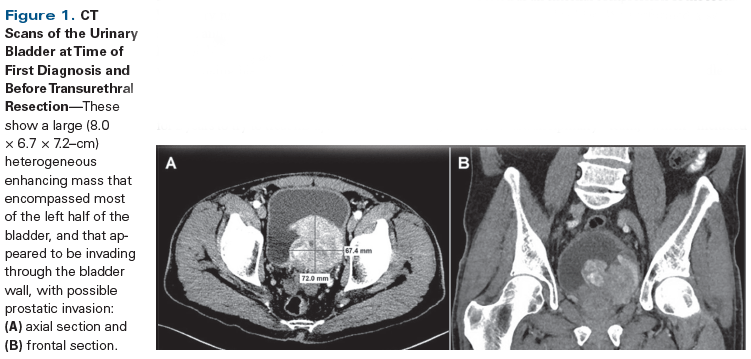

Figure 1. CT Scans of the Urinary Bladder at Time of First Diagnosis and Before Transurethral Resection

A 70-year-old man presented at our institution for a second opinion regarding diagnosis of a urinary bladder mass. He had a 3-year history of worsening urinary incontinence and urgency, for which he had undergone colonoscopy, as well as testing for prostate issues; all test results were negative. He experienced some improvement with tamsulosin. One month prior to admission, he was seen at an outside clinic for left flank pain; dysuria; gross hematuria; and intermittent episodes of diarrhea and constipation, with small stools. An outside chest/abdominal/pelvic CT scan with and without contrast showed a large, 8.0 × 6.7 × 7.2–cm, heterogeneous enhancing mass that encompassed most of the left half of the bladder and appeared to be invading through the bladder wall, with possible prostatic invasion (Figure 1). There was bilateral, mild ureterectasis, but no definitive hydronephrosis. No evidence of regional adenopathy or other suspicious distant lesion was observed. Significant laboratory findings included an elevated prostate-specific antigen (PSA) level of 5.6 ng/mL and a low hemoglobin level of 8.2 g/dL. He had a 20-pack-year smoking history and a family history significant for bladder cancer in his father. He had been taking a homeopathic colloidal silver medication for 2 years to try to treat his dysuria, and as a result, his partial thromboplastin time (PTT) was significantly elevated (42 to 60 seconds).